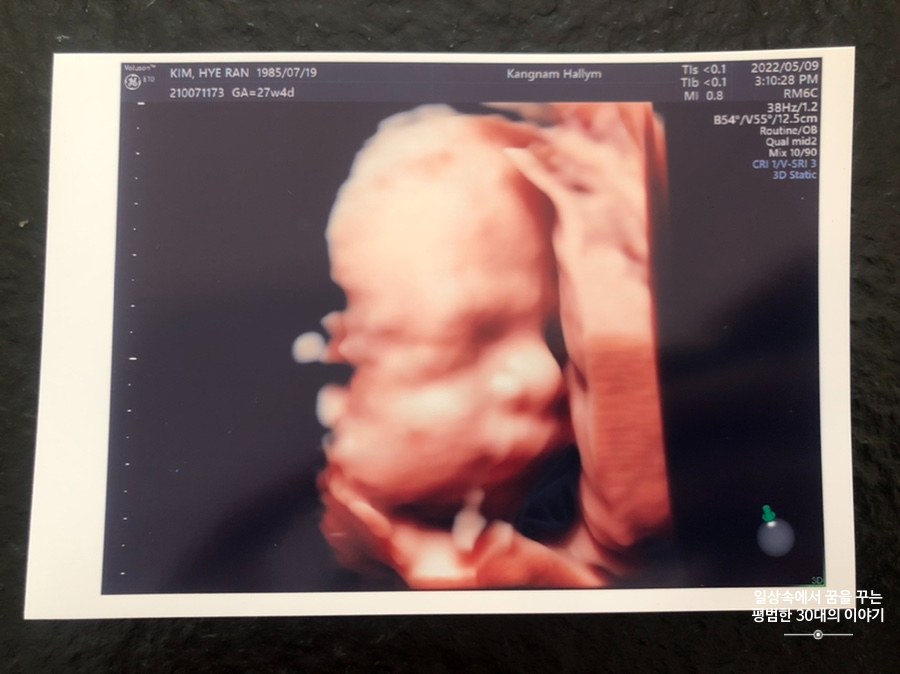

오늘은 입체 초음파 보는 날!!! 입체 초음파는 처음인데다 3주 만에 이안이 얼굴을 본다 생각하니 무척 설레는 마음으로 병원에 갔다. 첫 번째 시도에서는 계속 내 등 쪽으로 얼굴을 대고 엎드려 있어 실패! 초코우유 먹고 열심히 걸은 후, 30분 뒤에 다시 진행한 두 번째 시도에서는 얼굴 반쪽을 보여줬다. 얼굴 전면을 보지 못해 너무 아쉬웠지만 그래도 손가락 빨고 있는 모습, 웃고 있는 모습, 입 뻐끔 거리는 모습, 발차기 하는 모습, 손가락 쥐었다 폈다 하는 모습, 손을 휘적휘적 거리는 모습 등 다양한 모습을 보여줘서 그것만으로도 충분히 만족스러웠다. 내가 다니고 있는 강남성심병원은 입체 초음파가 다른 병원에 비해 무척 비싼 편인데(진료비 내역을 보니 초음파 진단료가 129800원 나옴) 그나마 위안을 삼을 수 있는 것은 화질이 그나마 좋은 편이라는 것이다.